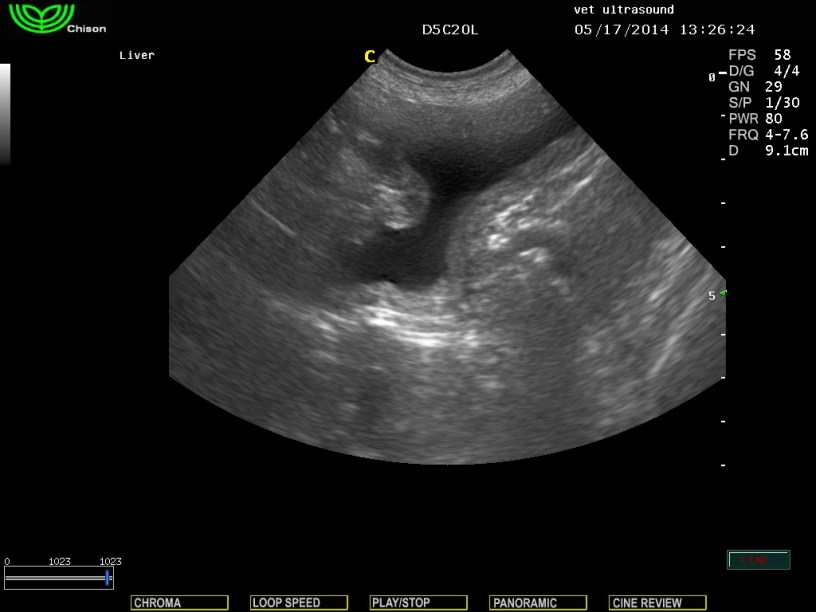

εδώ πάλι μετά τον καθετηριασμό σε επιμήκη τομή συμπιέζεται από τον σπλήνα και από το παχύ έντερο.